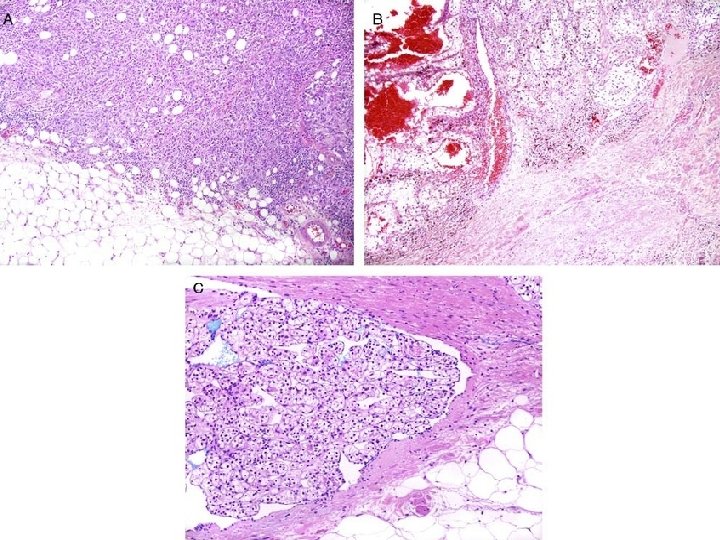

Invasione del grasso perinefrico (GP) • Il GP è il tessuto adiposo situato al di fuori della capsula renale ed entro i confini della capsula di Gerota. Molti RCC crescendo distorcono il profilo renale e premono sul GP. • La presenza di un un bordo tumorale arrotondato e liscio, di tipo espansivo, persino se chiaramente esteso oltre il normale profilo renale, non è diagnostica di invasione del GP. • L’infiltrazione può essere percepita macroscopicamente quando il tumore perde la sua interfaccia arrotondata e liscia con il GP o quando si osservano noduli o irregolari masse tumorali che protrudono nel GP. • Valutare sempre multiple sezioni perpendicolari dell’interfaccia tra tumore e GP (79%). • Per la conferma istologica è necessaria la presenza di tumore a diretto contatto con lobuli adiposi o la presenza di irregolari “lingue” tumorali nel GP, con o senza desmoplasia (71%).

Invasione del grasso perinefrico Bordi espansivi (A): no p. T 3 a Bordi infiltrativi (B): p. T 3 a

Invasione del grasso perinefrico Tumore a contatto con lobuli adiposi (A) Irregolari lingue tumorali, con o senza desmoplasia, nel grasso perinefrico (B)

Invasione del seno renale (SR) Il grasso del SR è il compartimento centrale del tessuto adiposo perinefrico, situato tra il sistema pielo-caliceale ed il parenchima renale. Contiene linfatici e numerose vene a parete sottile, tributarie della vena renale principale. Non c’è interposizione di capsula tra la corticale delle colonne del Bertin ed i vasi del SR.

Invasione del seno renale (SR) Nella passata decade numerosi studi hanno dimostrato che l’invasione del SR rappresenta la principale via di estensione extrarenale, specialmente per i carcinomi a cellule chiare. • Bonsib et al constatarono che >90% dei CC-RCC con diametro = o > 7 cm si associano ad invasione del SR. (J Urol 2015; 174: 1199 -1202) • Thompson et al riesaminarono il materiale residuo relativo a 33 nefrectomie radicali di pz. con CC-RCC, p. T 1, poi morti per la neoplasia; l’esame istologico dei nuovi prelievi relativi al SR mostrò la presenza di invasione dello stesso nel 42% dei casi. (Am J Surg Pathol 2007; 31: 1089 -1093) • Ci sono inoltre lavori che indicano che l’invasione del SR si associa ad una prognosi peggiore rispetto all’invasione del grasso perinefrico. (J Urol 2005; 174: 1218 -1221)

Invasione del seno renale (SR): come definirla? In casi dubbi andrebbero prelevate almeno 3 inclusioni dell’interfaccia tumore-SR (98%). Se l’invasione del SR è macroscopicamente evidente o assente (ad es. nel caso di piccoli tumori periferici) è sufficiente prelevare una sola inclusione per la conferma istologica. Istologicamente l’invasione del SR (p. T 3 a) è definibile quando: • il tumore viene a contatto diretto con il grasso del seno (100% ); • il tumore invade il connettivo lasso chiaramente situato oltre il parenchima renale (75%). • il tumore invade qualsiasi struttura vascolare presente nel seno renale, indipendentemente dalla taglia (90%).